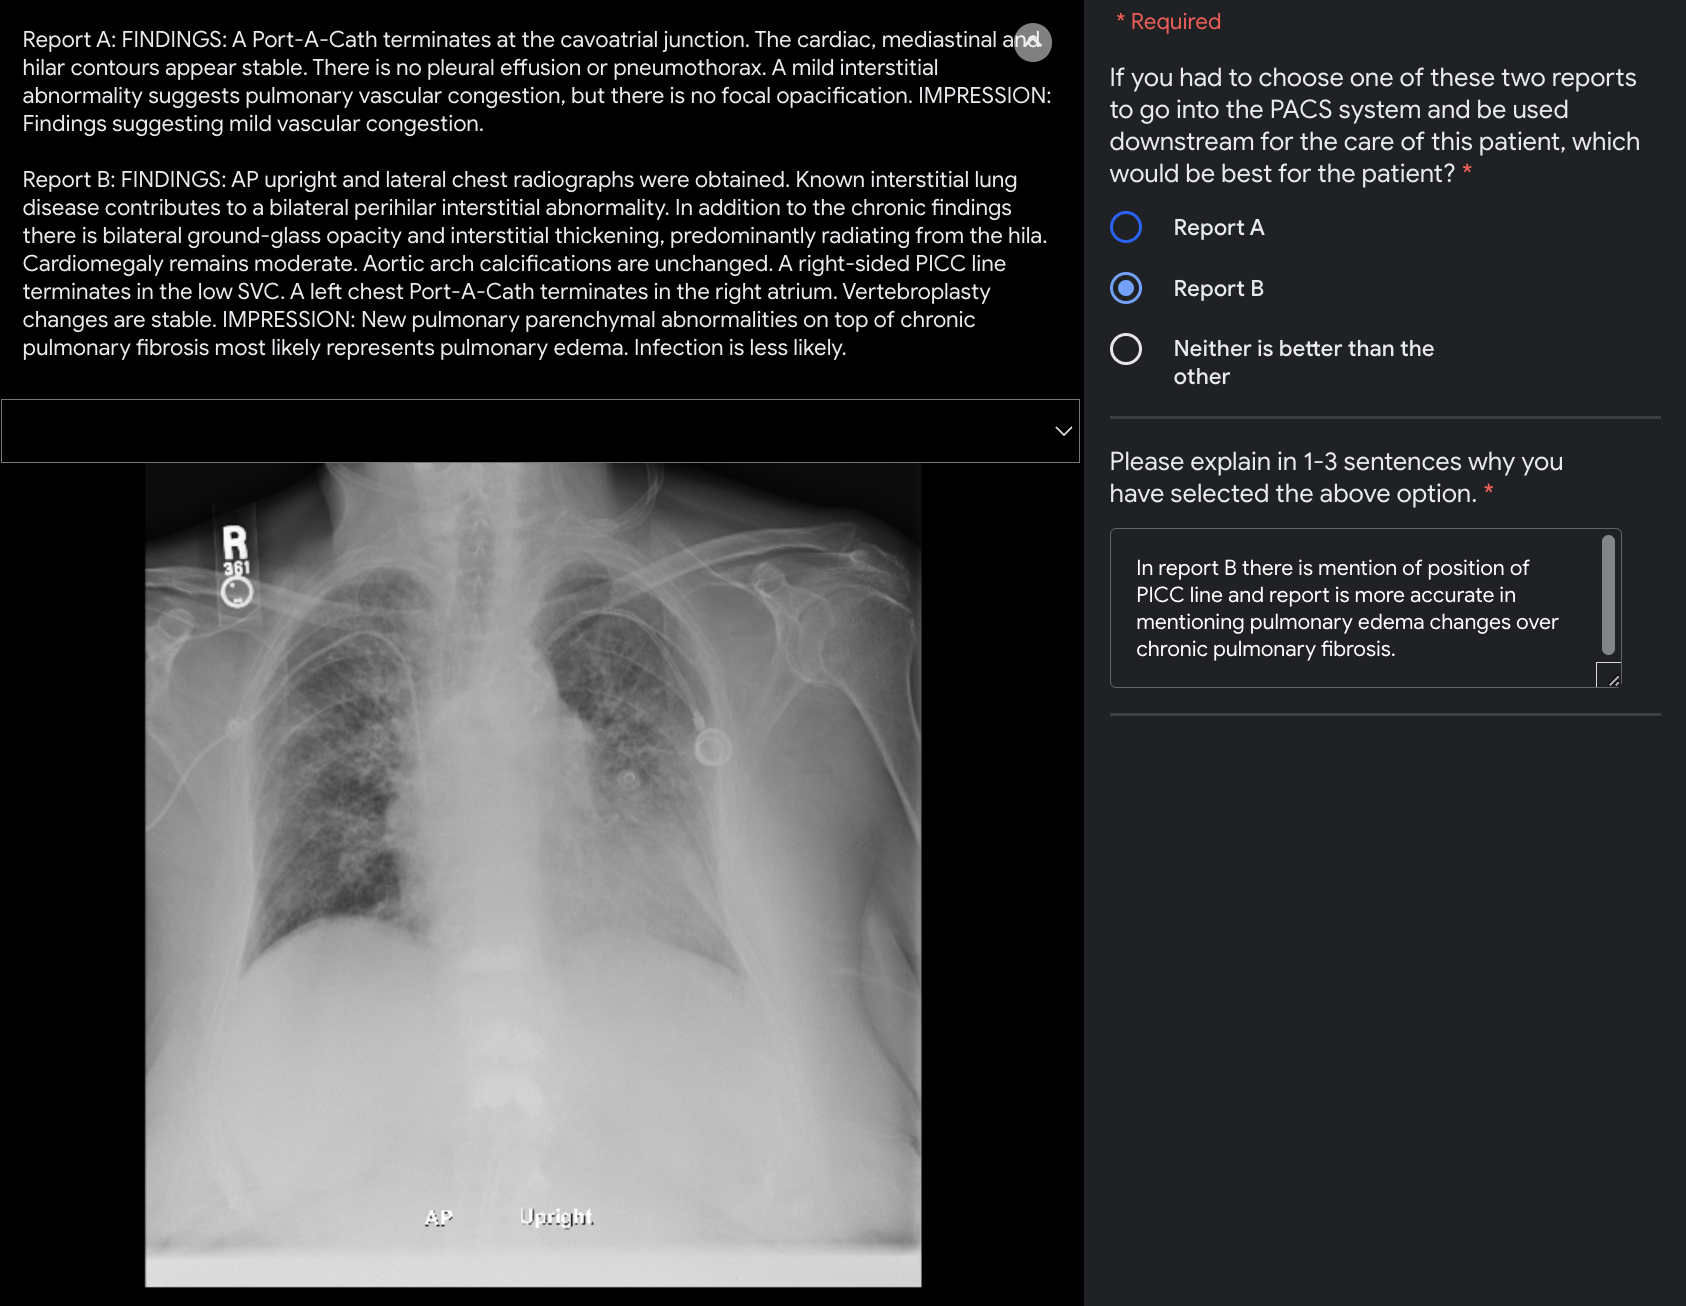

Refer to caption

Figure 8: Labelling interface for pairwise preference test. Raters are provided with (i) a frontal view (PA or AP) in the original resolution, (ii) a radiology report generated by our AI system and (iii) the original report written by a radiologist, and are asked to provide their preference. For each case, the raters are unaware of which report is the ground-truth and which one is generated by our model, and are requested to describe their preference out of three options; report A, report B, or equivalence between the two (i.e., “neither is better than the other”). The interface allows the raters to zoom in and out on the image as needed. They are additionally asked to provide an explanation for their choice.